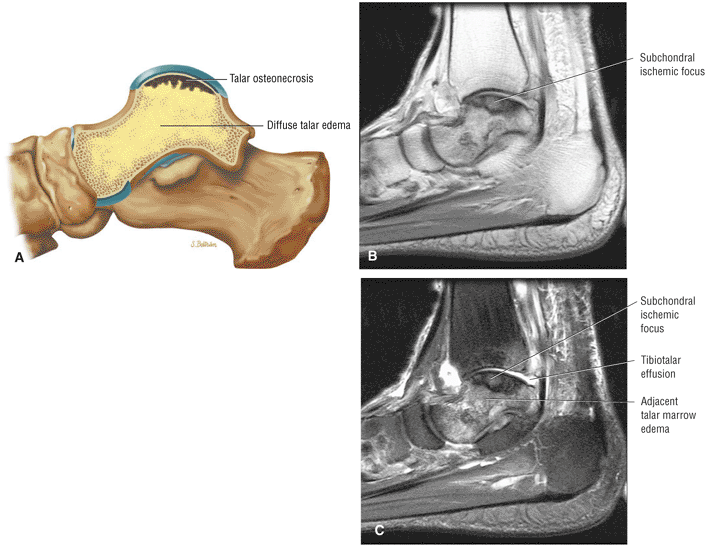

Stage I: Subchondral trabecular compression. Radiograph results are negative, bone scans are posi-tive, and marrow edema is seen on MR imaging (Fig. 5.95).

-

Stage IIA: A subchondral cyst (Fig. 5.96)

Stage IIB: Incomplete separation of the fragment (Fig. 5.97)

Stage III: Fluid around a nondetached, nondisplaced fragment (Figs. 5.98 and 5.99)

Stage IV: A displaced fragment (Fig. 5.100)